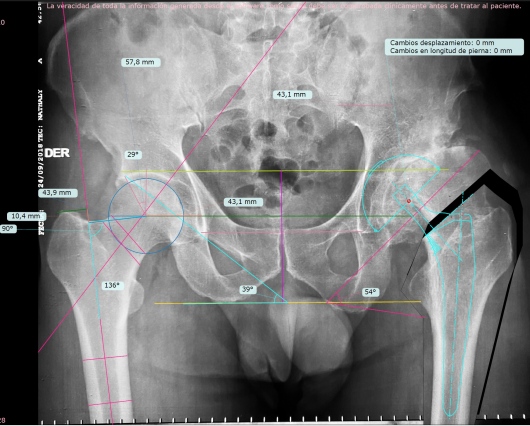

Practico una ortopedia centrada en usted como paciente, moderna, mínimamente invasiva y basada en evidencia científica. Me mantengo en constante actualización nacional e internacional y estoy certificado en cirugía de reemplazo articular con asistencia robótica con el sistema Mako® de Stryker, una tecnología de última generación para el reemplazo de cadera y rodilla, la más avanzada de Latinoamérica y el mundo.

Gracias a la planificación quirúrgica en modelos tridimensionales personalizados, este sistema permite una precisión milimétrica, lo que se traduce en:

Menor dolor postoperatorio

Incisiones más pequeñas

Mayor estabilidad de la prótesis

Recuperación funcional más rápida

Menor tasa de reintervención